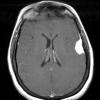

NEOPLASMS (MENINGIOMA)

Secretory (7)